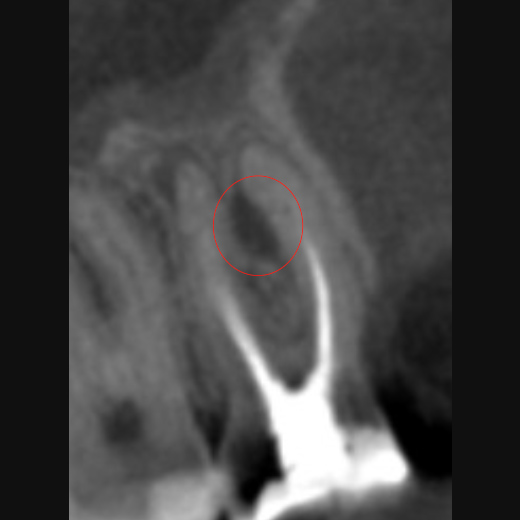

Perforationen bei einer Wurzelkanalbehandlung: Ist der Zahn noch zu retten?

Die Wurzelkanalbehandlung ist eine Therapiemöglichkeit, die höchstes Feingefühl erfordert und nicht immer läuft alles reibungslos. So kann es zu sogenannten iatrogenen Perforationen kommen: Das sind unbeabsichtigte Durchlöcherungen des Zahns, die zu unnatürlichen Verbindungen zwischen dem Wurzelkanalsystem und umliegenden Strukturen der Mundhöhle führen. Dadurch können Bakterien und Speichel in den Zahn eindringen, wodurch die Erfolgschancen der Behandlung verringert werden. Dies kann dazu führen, dass der Zahn gezogen werden muss.

Es gibt mehrere Möglichkeiten, Perforationen zu diagnostizieren:

So können z. B. 3D-Röntgenaufnahmen angefertigt und/oder mittels eines sog. Apex-Locators elektronische Kanallängenmessungen durchgeführt werden. Des Weiteren kann der Zahn mithilfe eines Dentalmikroskops inspiziert werden.

Bei der Perforation handelt es sich um die zweithäufigste Komplikation bei der Wurzelkanalbehandlung, doch in vielen Fällen stellt sie kein unlösbares Problem dar. Eine mögliche Abdeckung ist dabei stark von der Größe, Form und Lage der Perforation abhängig. Dabei gilt: Je kleiner und punktförmiger die Läsion, desto besser sind die Chancen, sie erfolgreich abzudichten. Zudem gibt es eine kritische Zone, in der Perforationen die schlechteste Prognose haben. Diese liegt im Bereich zwischen der Zahnfleischoberfläche und dem Beginn des Kieferknochens. Allerdings können eine kieferorthopädische Extrusion des Zahns oder eine chirurgische Kronenverlängerung zu einer erfolgreichen Behandlung dieser ungünstig liegenden Perforationen führen. Auch die Eigenschaften des Wurzelkanals selbst sowie der Zeitpunkt des Auftretens ist von Bedeutung.